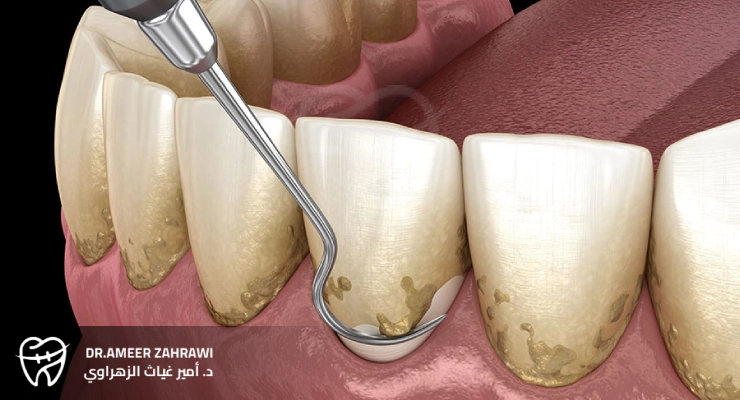

Dental scaling, often referred to as professional teeth cleaning, is a common dental procedure aimed at removing plaque and tartar (calculus) that build up on the teeth and along the gumline.During the procedure, the dentist or dental hygienist uses specialized instruments to carefully scrape away these hardened deposits, which cannot be removed with regular brushing or flossing. This process is essential for maintaining good oral health because it helps prevent gum disease, tooth decay, and other dental problems caused by bacteria accumulating in hard‑to‑reach areas.Having your teeth professionally cleaned on a regular basis—typically every six months as part of a routine dental check‑up—can play a major role in keeping your smile healthy and bright.

Dental scaling is a dental procedure carried out by a dentist or dental hygienist to remove plaque and tartar that have accumulated on the teeth and gums. The process typically includes the following steps:In general, dental scaling is a key part of preventive dental care and is essential for maintaining good oral health.

Tartar (calculus) is hardened plaque that forms on the teeth when plaque is not adequately removed through regular brushing and flossing. The presence of tartar can lead to several negative effects on oral health: